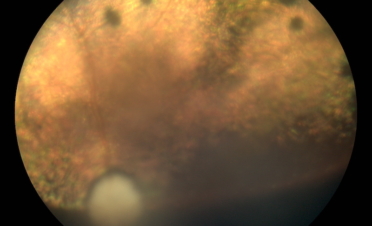

Retinografías de Fox, un perro de raza Pomerania con desprendimiento de retina en ambos ojos. Foto: IVO. (Clicar la fotografía para ampliar).

En ambas pruebas se observaron imágenes compatibles con un desprendimiento de retina:

Al examinarlo se confirmó ceguera aguda y se observó un desprendimiento de retina bilateral, posiblemente de causa genética, ya que no había sufrido ningún traumatismo conocido.

Se le realizó una ecografía y una retinografía para confirmar el diagnóstico.

La retinografía permite, a modo de fotografía, obtener imágenes en color de la retina. Es una prueba que proporciona una información muy valiosa sobre el estado de la retina y el nervio óptico.